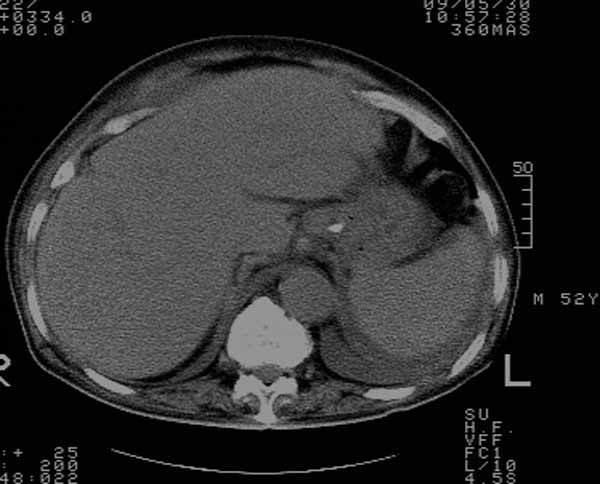

标题: 胆囊阴性结石ct图片

好啊!我有ct的插进来啊,楼主请允许噶。

[本贴已被 zjh196425 于 2009-5-27 14:28:33 修改过]